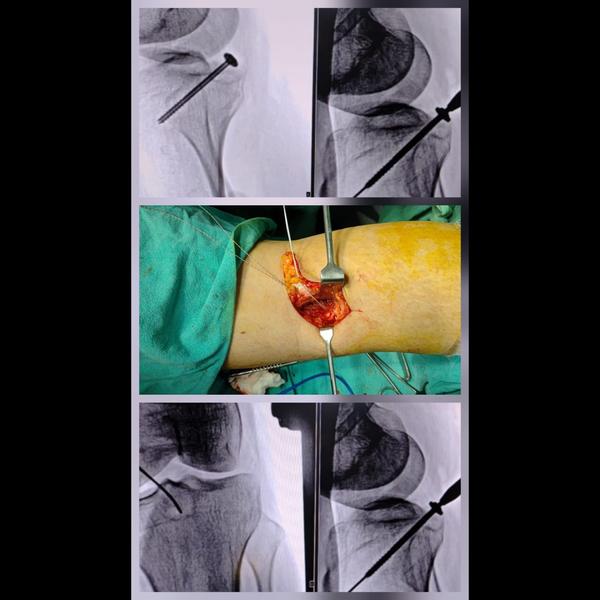

ACL graft preparation !

View Details